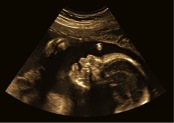

Ernia diaframmatica, stenosi della valvola aortica, complicanze delle gravidanze gemellari: sono alcune delle gravi patologie fetali operabili oggi in endoscopia prima della nascita. Ma la nuova frontiera riguarda la spina bifida. “Dal 2017 sarà possibile anche in Italia operarla nel feto ancora in utero con un’operazione mini invasiva”. A spiegarlo all’ANSA è Isabella Fabietti, del Centro di Chirurgia Fetale della Clinica Mangiagalli del Policlinico di Milano, intervenuta oggi al convegno “US-Italia. Patient Day 2017”, organizzato presso l’Ambasciata degli Stati Uniti in Italia.

Anomalia fetale congenita che spesso porta i genitori a scegliere una interruzione di gravidanza anche in stadio avanzato, la spina bifida può provocare paralisi degli arti inferiori, incontinenza urinaria, idrocefalo. Questo, spiega l’esperta, “è dovuto al fatto che la parte terminale del spina dorsale non è chiusa correttamente e il midollo viene a contatto con il liquido amniotico. Più tempo trascorre a contatto, più gravi i danni.

Oggi si opera dopo la nascita ma i danni sono ormai irreversibili. Intervenire nel secondo trimestre di gestazione permette di diminuire le conseguenze”. È quello che sarà possibile grazie a dispositivi high tech che consentono di operare in utero in endoscopia, una tecnica già applicata dal team della Mangiagalli in casi di gravi malattie che richiedono intervento chirurgico immediato sul feto. “Oggi siamo in grado di ridurre notevolmente i danni provocati da ernia diaframmatica fetale, che provoca lo schiacciamento dei polmoni da parte degli organi digestivi.

Anche in questo caso, intervenire prima significa ridurre i danni”, prosegue Fabietti. Per offrire un servizio di consulenza rivolta a medici e pazienti così da estendere a quanti più bimbi possibile le novità dell’endoscopia fetale, è a disposizione la app “Chirurgia Fetale”, scaricabile gratuitamente e messa a disposizione dalla Clinica Mangiagalli, centro all’avanguardia in Europa nel settore.